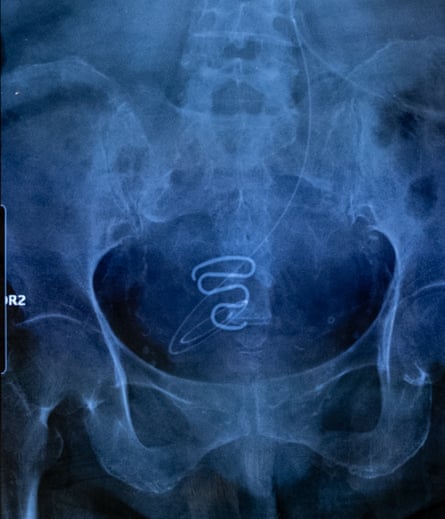

An X-ray showing an IUD or coil – commonly known as a ‘spiral’ – used during the forced contraception campaign.

These IUDs were far too large and unsuitable for the bodies of young teenage girls. In addition to the pain and bleeding, the spirals sometimes caused serious infections that have made some victims permanently sterile.